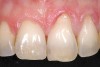

A 54-year-old non-smoking woman presented for correction of deep-wide gingival recession in the maxillary anterior (Figure 1 through Figure 3). The patient’s desires were to correct the gingival recession, balance the heights of contour of the tissues, and possibly undergo esthetic enhancement of the maxillary anterior with veneer restorations.

Figure 1  Case One Pretreatment clinical view, Case 1, maxillary right.

Figure 1